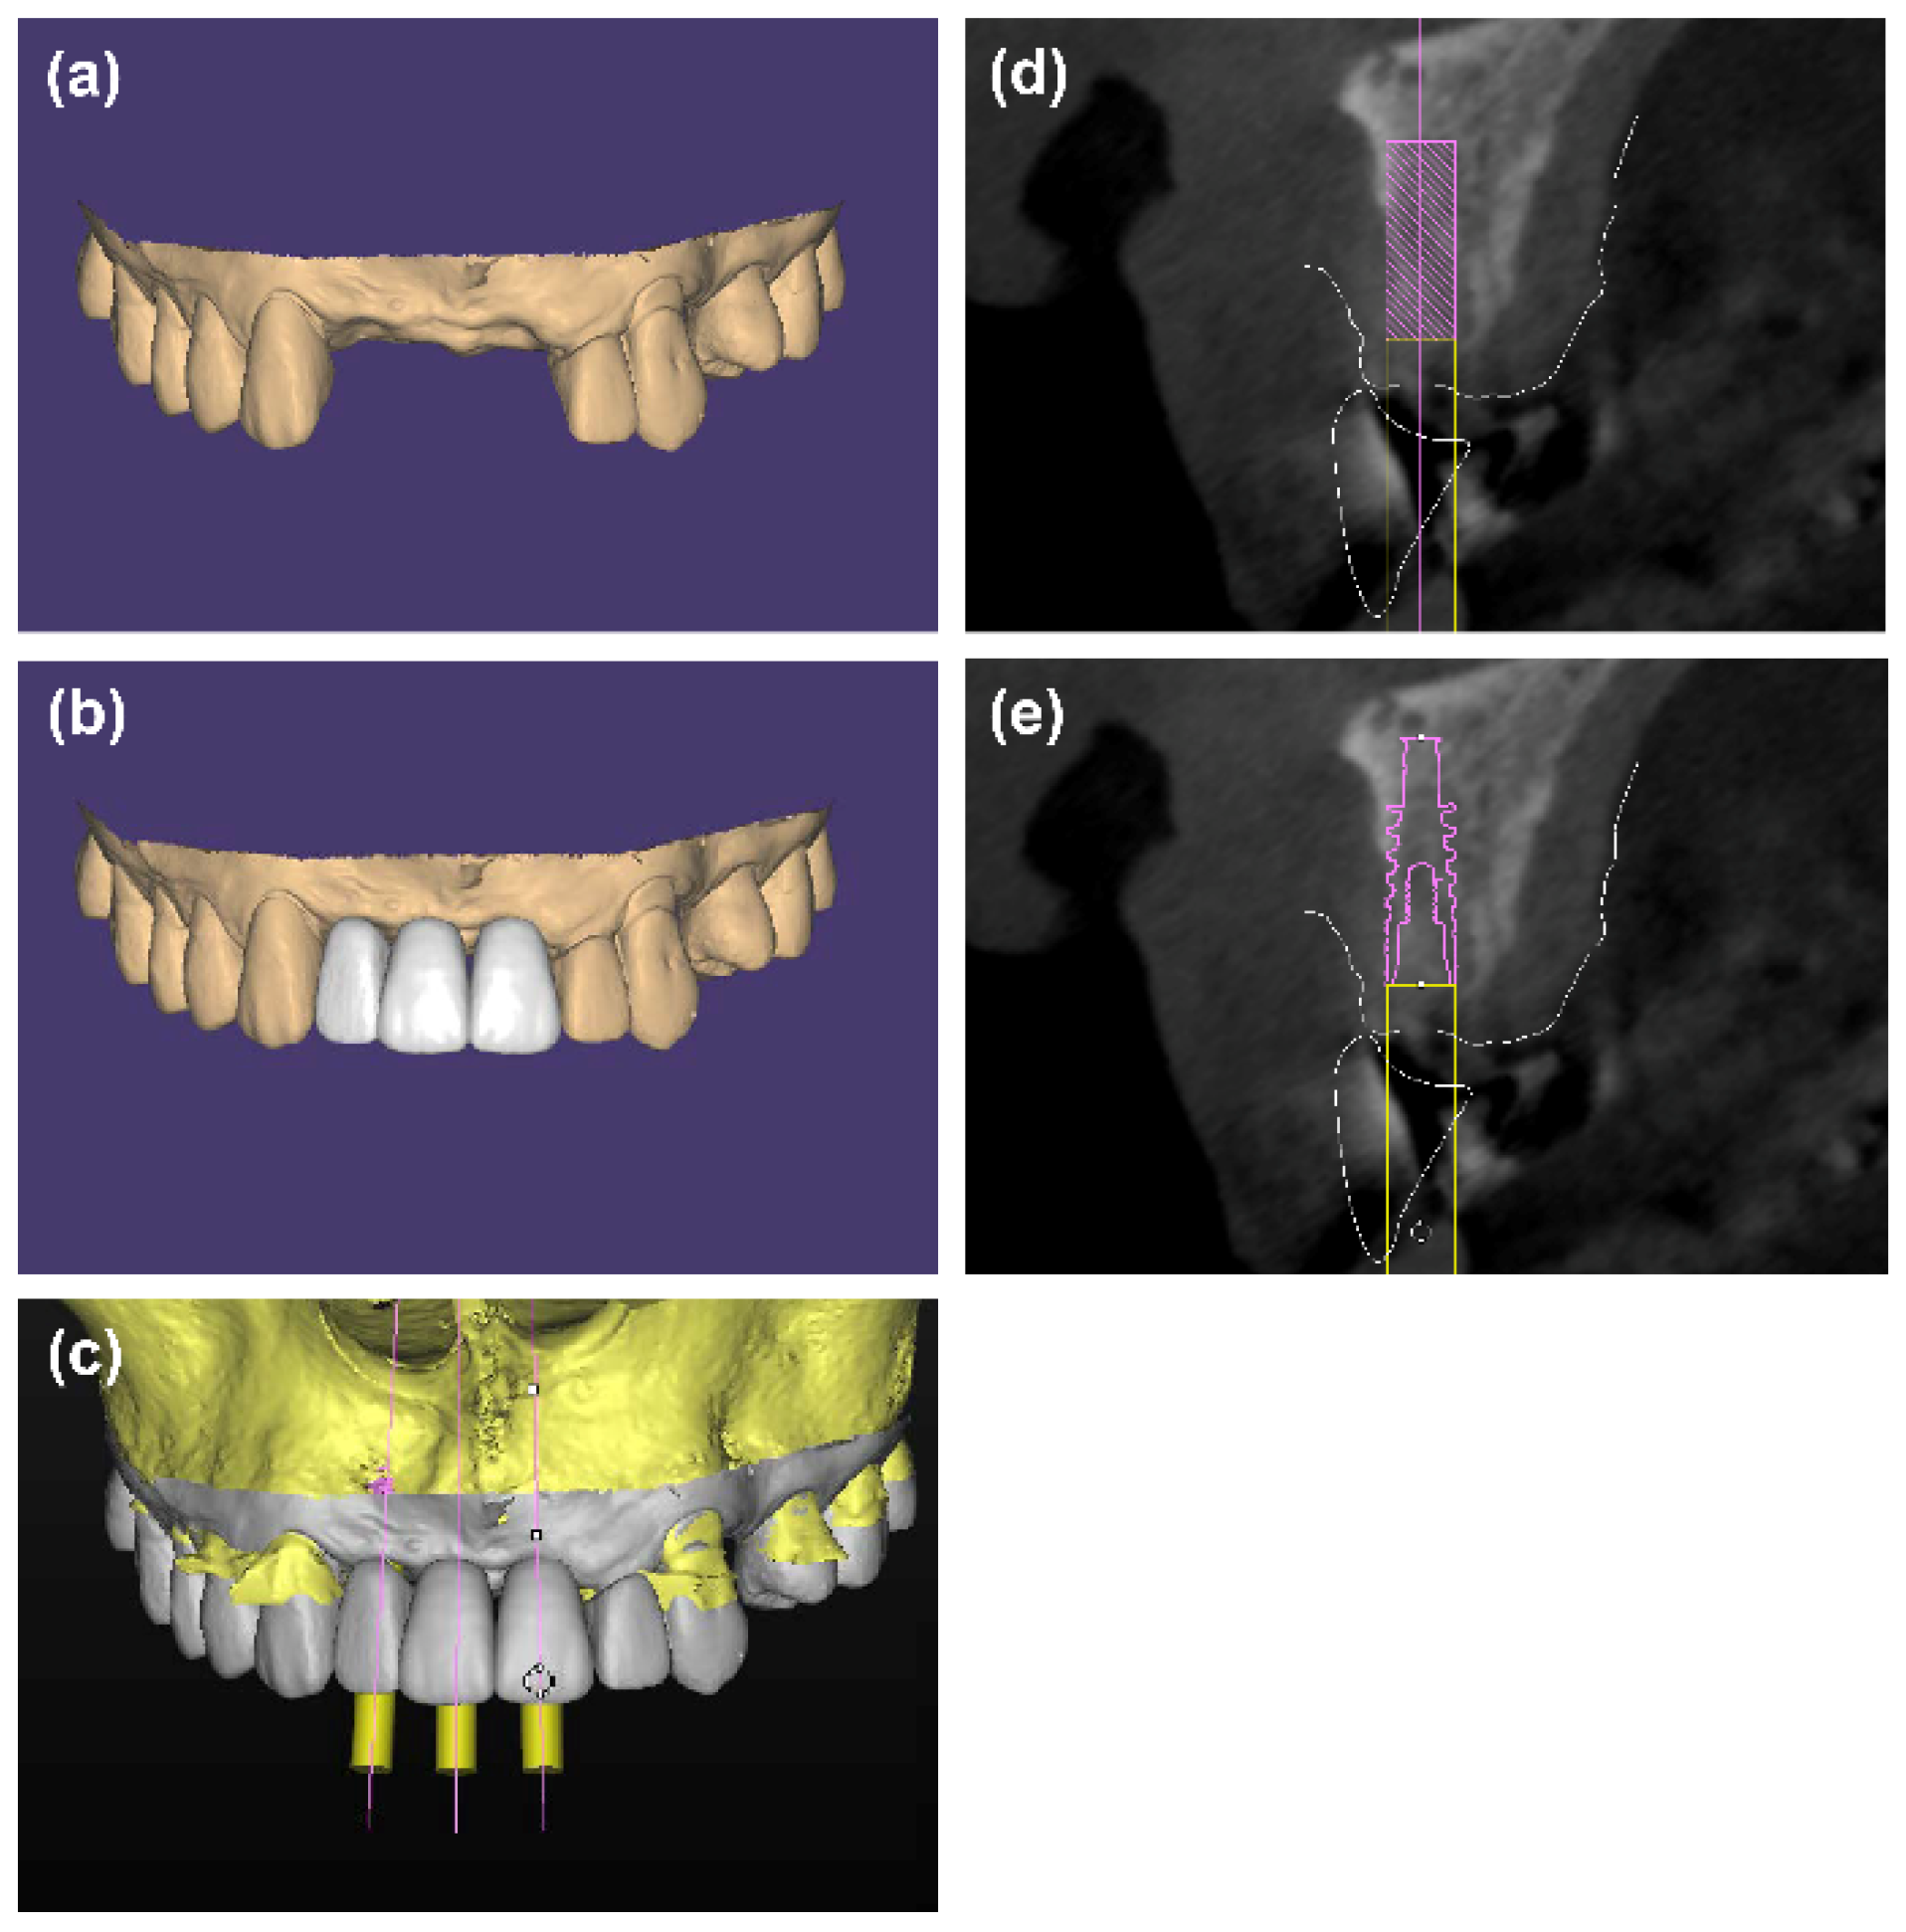

An intraoral scan was performed before surgery for preoperative design (3Shape TRIOS®, 3Shape, Copenhagen K, Denmark) and a diagnostic wax-up was generated on the intraoral scan. Then the standard tessellation language (STL) files of the intraoral scan and diagnostic wax-up were overlapped above the DICOM files of the preoperative CBCT images in Simplant software (Simplant Pro 17.01, Dentsply Sirona, York, PA, USA). Virtual implants of 3.5 mm diameter and 10 mm length were placed under the guidance of the ideal future implant restoration [22,23]. Data of preoperative design were saved as an SPR file, which was named “baseline.spr”.

A copy of “baseline.spr” was created, and the 3.5 mm diameter and 10 mm-length virtual implants were replaced with specific virtual implants (Bone Level Titanium SLA, Institut Straumann AG, Basel, Switzerland; NobelActvie, Nobel Biocare, Göteborg, Sweden) of proper size. The patients were free to choose implant systems according to their own will. The direction, labial position, and depth of the specific virtual implants were the same as the 3.5 mm diameter and 10 mm-length virtual implants (Figure 1). A tooth-supported surgical guide plate was fabricated based on the copy of “baseline.spr”.

Figure 1.

(a–d) 3.5 mm diameter and 10 mm-length virtual implants were placed in a prosthetically ideal position under the guidance of the diagnostic wax-up. (e) The 3.5 mm diameter and 10 mm-length virtual implants were replaced with specific virtual implants of the proper size to fabricate the surgical guide plate for implant placement.